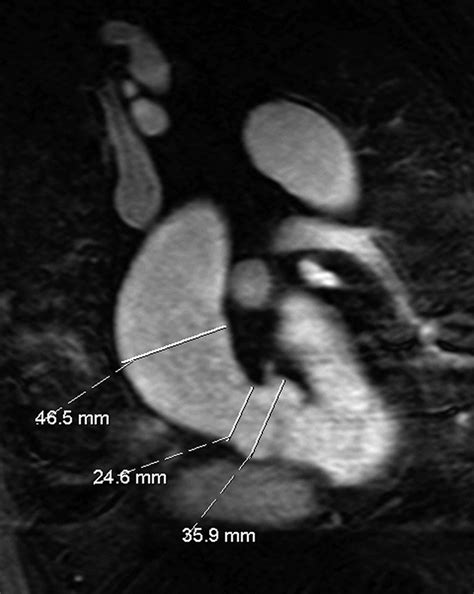

CT Angiography (CTA) Uses contrast dye to create detailed 3D images of the aorta.

Magnetic Resonance Angiography (MRA) Offers highly accurate measurements without exposure to ionizing radiation.